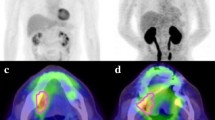

During radiotherapy, the maximum decline in T/NT measured for FDG and FLT was 42 ± 18% (scan 3) and 49 ± 16% (scan 4; mean ± SD), respectively. At all time points, FLT uptake was higher than that for FDG, but FDG uptake showed less variation. For FLT, the decrease seen in the first week was followed by a much larger decrease in the second week (Fig. 3a, b). For FDG as well as for FLT, a significant decline in retention (relative T/NT ratio) was observed at scan 2 (day 4). Next to this observation, for FLT, the most significant decline in retention (relative T/NT ratio) was observed at scan 4 (day 12), whereas for FDG, this was already noted from scan 2 (day 4). Table 3 summarizes the results from the statistical analyses correlating T/NT and changes in T/NT (ΔT/NT) to tumor volumes at baseline (V baseline) to exclude differences in the initial situation and at day 29 (V day29). For FDG, no statistical significant correlation was found between V baseline and any of the T/NT values. In contrast, for FLT, statistical significant correlations were found for both V baseline and V day29 with T/NT and ΔT/NT of scans 2 and 3. Statistical significance disappeared with respect to scan 4 possibly because of the 4-day period between the last radiotherapy and scan 4. For FDG, only a significant correlation was found between V day29 and T/NT baseline. A predictive effect of baseline tumor volume was not found.

To study response monitoring in the HNX-OE xenograft model, a protocol was designed mimicking conventional clinical radiotherapy protocols, with the view of predicting effects of radiotherapy as soon as possible. From FDG studies, it is known that, in general, changes in FDG signal appear before changes can be detected in tumor volume [34]. For FLT, however, little is known. Based on the radiosensitivity experiments, it was assumed that fractionated radiotherapy with a total dose of 22 Gy would result in an adequate radiation dose for determination of the time course of FDG and FLT signals after radiotherapy under conditions that are relevant clinically. Indeed, a significant reduction in tumor volume was observed after this treatment. Tumor growth curves in both FDG and FLT groups followed a similar pattern over time. FLT uptake was, however, higher then that of FDG, and both FDG and FLT uptake showed rapid response to radiotherapy. The decrease in FLT uptake as seen in the first week was followed by a much larger decrease in the second week, which was not the case for FDG uptake. For FDG as well as for FLT, a significant decline in retention (relative T/NT ratio) was observed at scan 2 (day 4). Next to this observation, for FLT, the most significant decline in retention (relative T/NT ratio) was observed at scan 4 (day 12); whereas for FDG, this was already noted from scan 2 (day 4). Statistical significance disappeared with respect to scan 4 possibly because of the 4-day period between the last radiotherapy and scan 4. In a study of Sugiyama et al. [35], C3H/He mice, bearing SCCVII tumors (murine SCC), who received a single dose of 20 Gy, showed a rapid response to radiotherapy both with respect to FDG and FLT uptake in line with the present results.